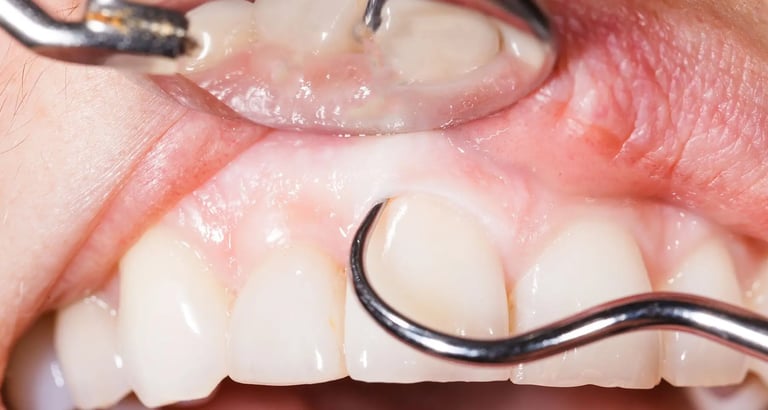

Deep Cleaning, also called Scaling and Root Planing (SRP), is a non-surgical treatment for gum disease. During this procedure, the hygienist cleans deep under the gums and smooths the roots of your teeth. This reduces inflammation, stops infection from getting worse, and helps gums heal and reattach to the teeth.

Deep cleaning, also known as scaling and root planing, is used to treat gum disease by removing plaque and bacteria from below the gum line and smoothing the tooth roots to help gums heal properly. Depending on the severity of the condition, the treatment may be completed in sections (such as half-mouth or quadrant visits) to ensure comfort and thorough care. After deep cleaning, ongoing periodontal maintenance visits every 3–4 months are essential to keep gum disease under control, as regular cleanings are not sufficient once periodontal issues are present.